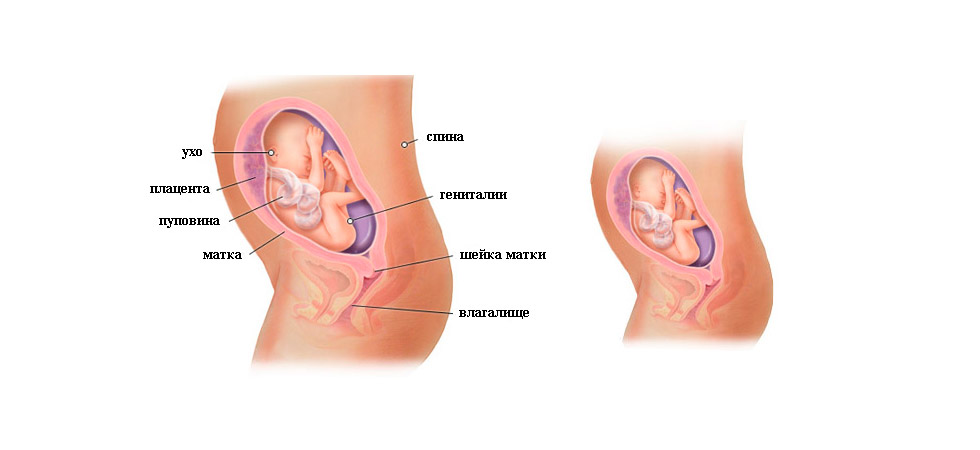

Что определяют на УЗИ

На 22-й неделе проводится второе скрининговое УЗИ, если оно не было назначено немного раньше. В отличие от первого скрининга, сейчас анализы крови не являются обязательными, если в прошлый раз не было выявлено риска рождения ребёнка с аномалиями развития. В ходе исследования врач определяет положение малыша в утробе. Оно может быть:

- тазовым;

- поперечным;

- головным.

На 22-й неделе на УЗИ хорошо просматриваются контуры тела малыша

Оптимальным вариантом является головное предлежание, когда малыш занимает позицию головой вниз и вверх ножками. Если он сидит на попе или лежит на боку, не нужно расстраиваться, ведь ещё есть время и место в полости матки, чтобы перевернуться

Однако специалисты обращают внимание на положение плода уже сейчас. А также доктор изучает развитие жизненно важных органов, частей тела малыша, оценивает его рост и массу, соответствие гестационному сроку развития

Нормальными считаются следующие показатели:

- БПР (бипариетальный размер, измеряемый от одного до другого виска головы) – 48–60 мм;

- ОГ (окружность головы) – 64–76 мм;

- ОЖ (окружность живота) – 148–190 мм.

Оценивается также состояние матки на предмет тонуса, состояние и расположение плаценты, степень её зрелости

Немаловажное значением имеет количество околоплодных вод

На 22-й неделе на УЗИ хорошо видно, кого ждёт женщина, конечно, при условии доступного для датчика расположения половых органов плода

Женщина ощущает, что ее внутренние органы уже изменили свое положение из-за роста матки.

Это могут быть не только чувства давления или растягивания связок и мышц брюшной полости, но и явные симптомы: запоры, связанные с ухудшением перистальтики кишечника, вздутие живота из-за задержки пищи в желудочно-кишечном тракте, быстрое переполнение мочевого пузыря.

Живот на 22 неделе беременности

Живот на 22 неделе вполне заметен. Его форма может немного меняться в зависимости от того, в каком положении находится ребенок. А поворачивается плод в животике довольно часто: у него для этого еще достаточно места. Увеличивается не только живот, но и молочные железы, и отложения подкожной жировой клетчатки на бедрах.

Все части лица уже хорошо сформированы. На глазках есть веки, которые приоткрываются. Выросли реснички и бровки, которые иногда хмурятся. Мимика ребенка пока не сознательна. Если сделать УЗИ в 22 недели, будет видно не только, что происходит с плодом, но и все его структуры лица. Причем, если малыш займет удобное для врача положение, уже можно будет понять, на кого из родителей он больше похож, чей у малыша рот или нос. На память можно будет сделать фото и видеозапись.

На этом сроке уже проводят допплерометрию — то есть смотрят состояние кровотоков ребенка. Если есть нарушения — может потребоваться стационарное лечение. Иногда нарушения бывают критическими, и тогда определяется значительная задержка развития плода, гипоксия. Обычно симптомом этого является медленный рост обхвата живота и высоты дна матки, а также слабые и редкие шевеления ребенка.

При допплерометрии оценивается кровоток в артериях пуповины. Эти показания являются важнейшими характеризующими маточно-плодово-плацентарного кровообращения.

Кроме допплерометрии, на УЗИ в двадцать две недели гестации смотрят структуру плаценты. Она должна иметь однородную структуру. Возможно небольшое расширение межворсинчатых пространств. Данная особенность характерна для женщин, у которых часто бывает пониженным артериальное давление. Степень зрелости плаценты пока нулевая. Если врач ставит уже первую, это означает, что есть риск развития фетоплацентарной недостаточности, внутриутробной задержки развития плода. И, возможно, потребуется сделать перед третьим скрининговым УЗИ еще одно, контрольное, чтобы оценить кровотоки плода.